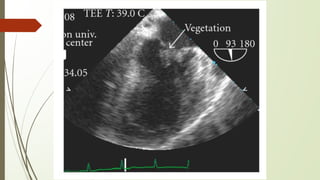

ECHOCARDIOGRAPHY